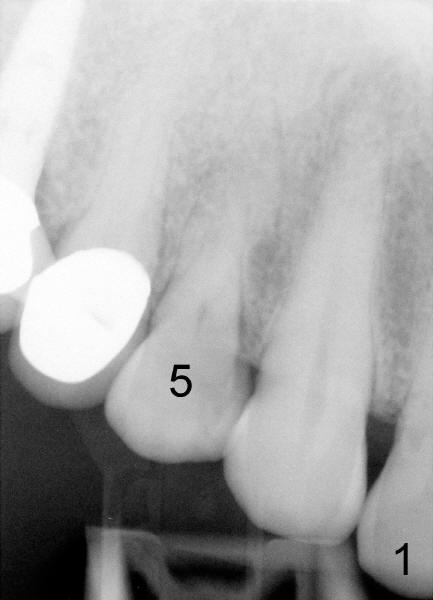

Sixty-eight year old healthy man has had multiple implants.  He readily accepted immediate implant when the tooth #5 had subgingival fracture of the lingual cusp (Fig.1).  A 5x20 mm Tatum screw implant was placed immediately after atraumatic extraction and bone expansion (Fig.2 I).  Implant rough surface was exposed buccally and lingually when the implant was placed equigingivally proximally.  Two buccal accessory incisions were made.  The flap was raised with scoring the periosteum underneath, advanced downward (as shown in Fig.3 arrow) and sutured to the lingual papilla.  The buccal aspect of the implant is covered, whereas the lingual rough surface remains partially exposed (Fig.4 arrow), assuming that the palatal mucoperiosteum is tough to advance even with release incisions.